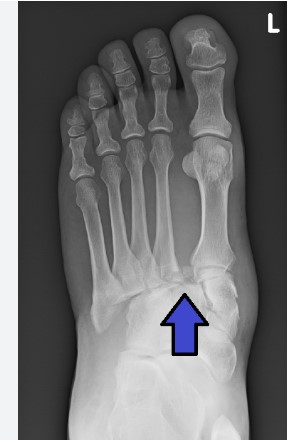

Fracture guide